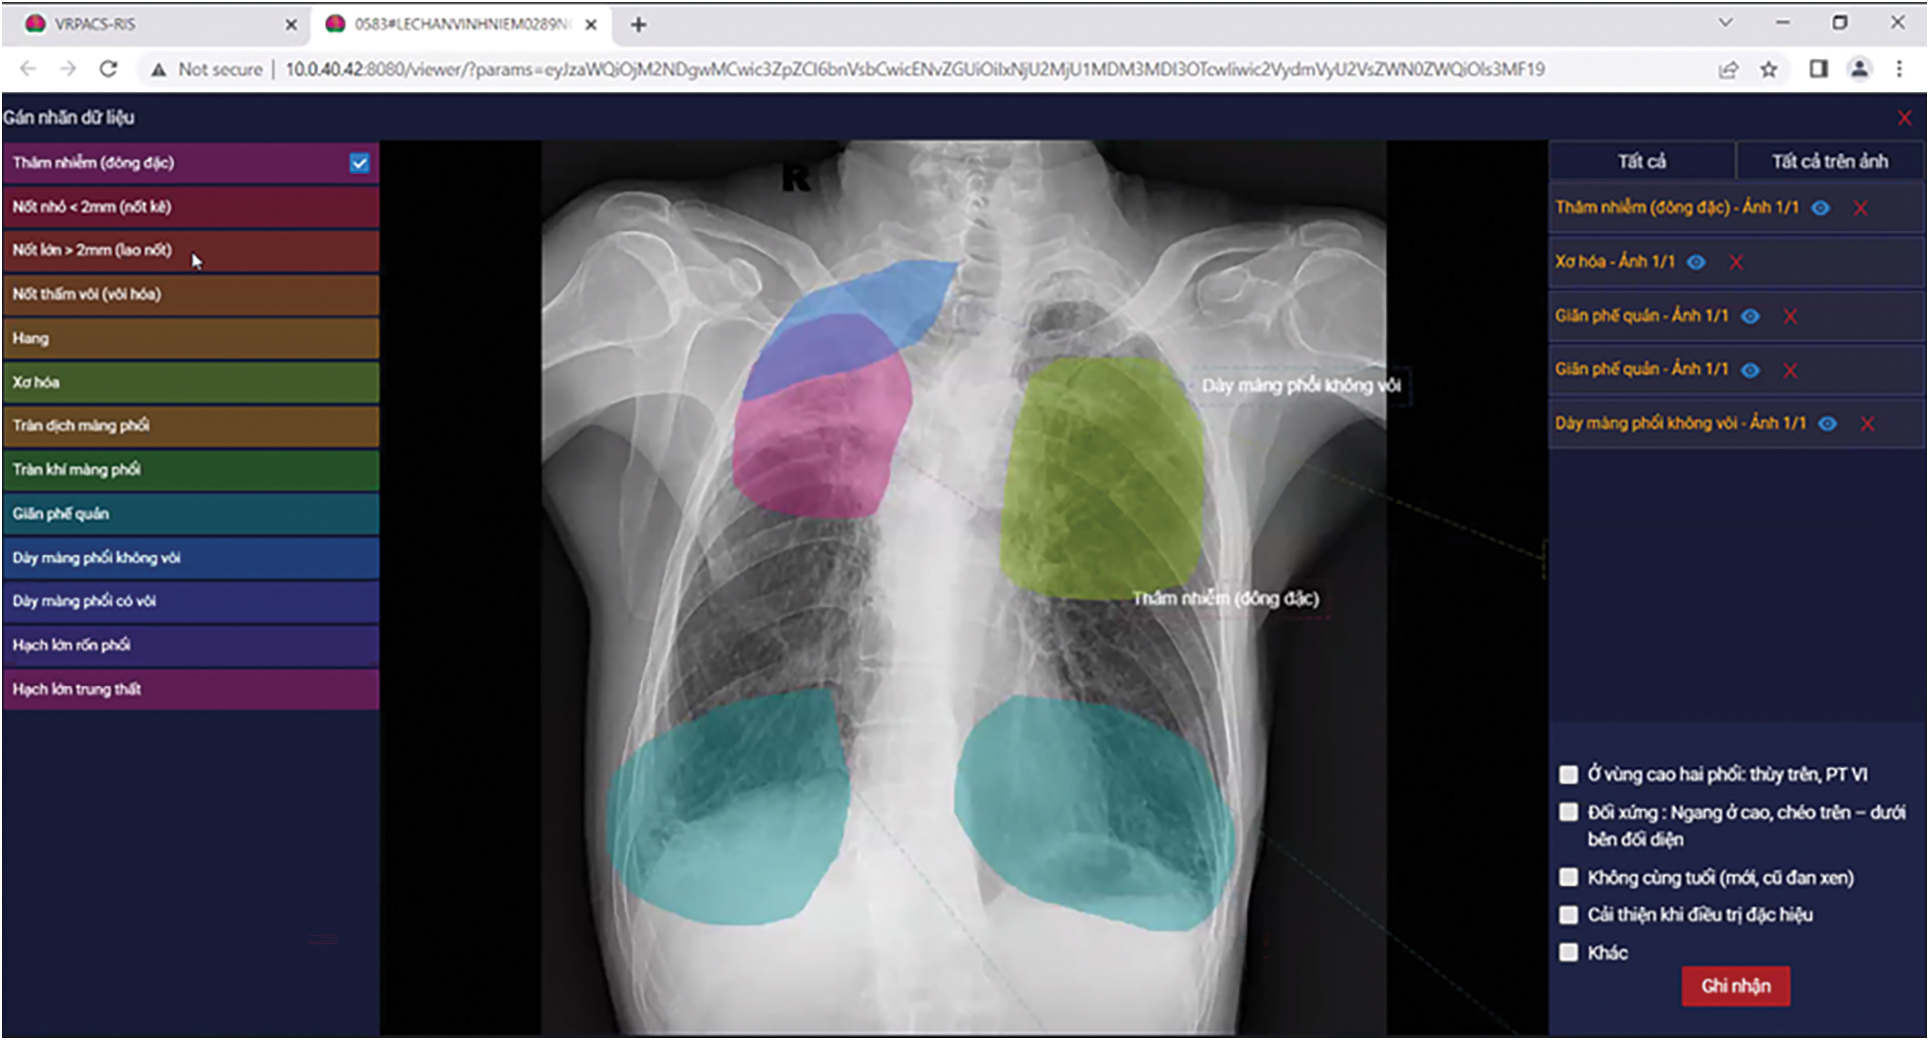

To support the radiologist’s annotation task, we built the annotation software. This software connects to the VRPACS server at the Vietnam National Lung Hospital. The radiologists choose chest X-ray images from this dataset to annotate. In the beginning, each image has a “NO READ” state. After the radiologists annotate, the state changes to “COMPLETED”. In the software interfaceas described in Fig. 4, there are controllers to indicate specific information about tuberculosis. The radiologists would use a computer mouse to choose the specific lesion type and draw the boundaries of that region.

Figure 4: Our annotator software interface

All tuberculosis annotation specification was analyzed and designed following the doctor’s comments as described in Table 3. Firstly, the radiologists listed all symptoms of tuberculosis on the chest X-ray image based on the knowledge they use when they examine patients. These symptoms would be the annotation types in the annotation software. Secondly, the software interface would be designed so radiologists can conveniently annotate. The doctors would open the chest X-ray image, use a mouse to choose regions of symptoms and select the annotation type.

There are some difficulties when designing the annotation specification also the annotation software. Software engineers and radiologists have a difference in their knowledge. On the one hand, software engineers need to learn the causes and progression of tuberculosis. On the other hand, several radiologists are not proficient in using computer software and are even quite old. It is rather difficult for them to use a mouse and keyboard to select exactly the boundary of symptoms on the chest X-ray images. Sometimes, they have to sit together and a software engineer manipulates the annotation software under instructions from a radiologist.